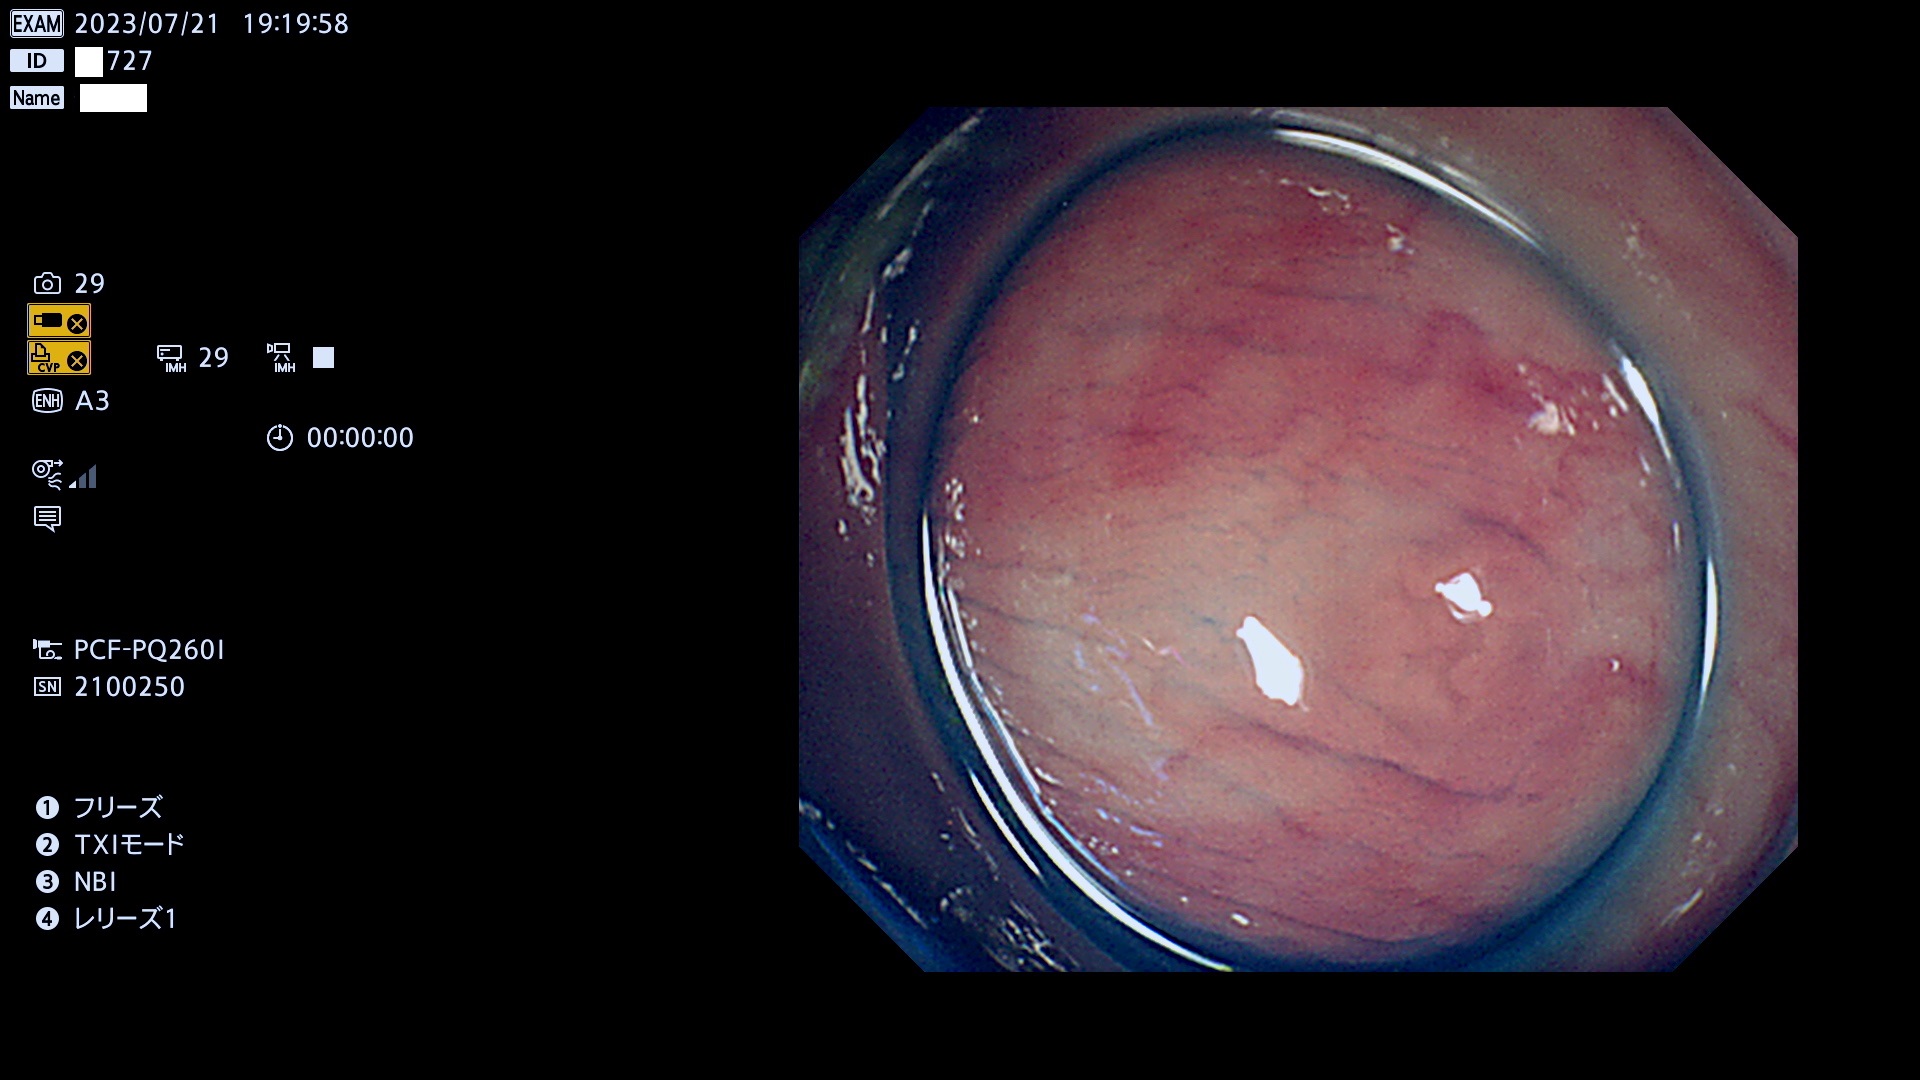

「表面型腺腫(Flat Adenoma)の中で、完全に平坦な物をUb、陥凹している物をUcと呼びます。平坦隆起型(Ua)よりも、発見が難しく危険な病変です。このタイプは「内視鏡後・大腸癌の重要犯人」であり、この発見率は「腺腫発見率」よりも、重要な意味があります。

毎週の検査(木・金・土・日)に発見されたUb、Uc型・腺腫を、その週の日曜の夜にUPし1週間、提示します。

抽出の対象期間 2023年7月20日(木)〜7月23(日)の4日間(48件の検査)12件